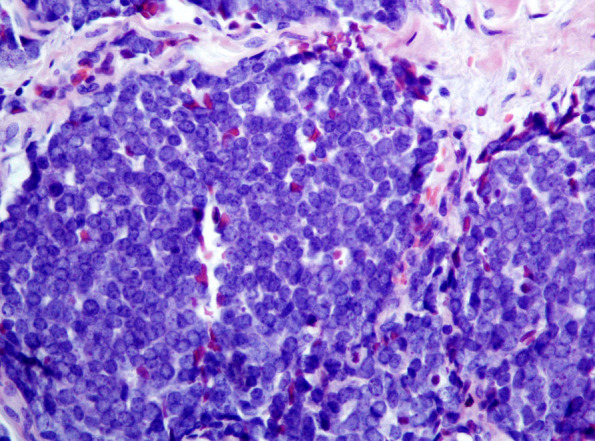

第5版世界卫生组织皮肤肿瘤分类(2022)对命名和诊断进行了修改。以下讨论了重要差异。每一类皮肤肿瘤的变化都有详细的描述,特别强调我们对皮肤不同肿瘤景观的分子发病机制的理解取得了有意义的进展。

The 5th edition WHO Classification of Skin Tumors (2022) has introduced changes to nomenclature and diagnostics. Important differences are discussed below. Changes in each category of skin tumor have been detailed, with particular emphasis on meaningful advances in our understanding of the molecular pathogenesis of the skin's diverse tumor landscape.